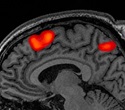

This pilot study is based on a new approach - training individuals to use neurofeedback to modulate their pain using real-time fMRI of the anterior cingulate cortex --the area of brain associated with pain. This technique of fMRI neurofeedback has been studied in other populations with chronic nerve-based pain, according to Dr. Zanca, and has helped them reduce their pain sensations by self-controlling brain activity. "We will see whether this technique helps people with spinal cord injury learn thinking strategies that they can use in daily life to reduce the intensity and unpleasantness of their pain," she explained.